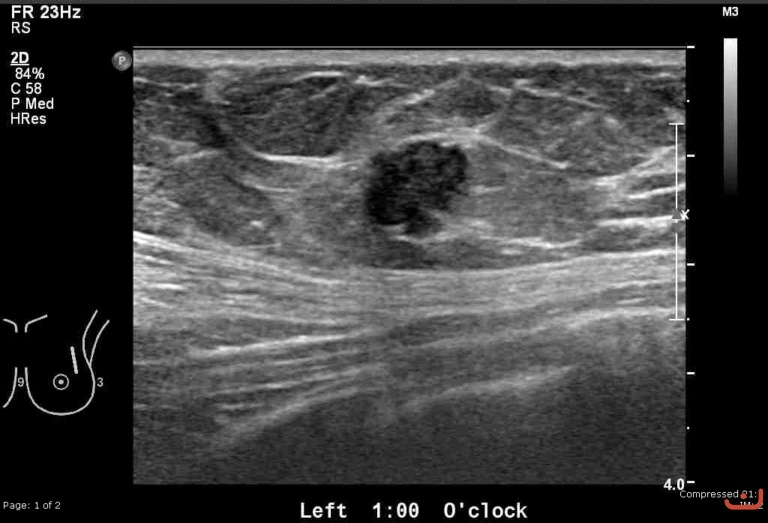

Malignant solid mass

Date

Thursday, 30 April 2015

187.75 KB (768 x 523 px)